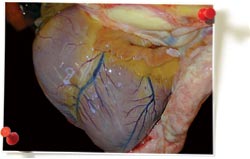

Sérosite (mono ou polysérosite)

Infection bactérienne systémique touchant une ou plusieurs séreuses. Il peut s'agir de lésions de type fibrineux (aiguës), dans lesquelles il est logique d'essayer d'isoler l'agent responsable ou de lésions de type fibreux (chroniques), où l'agent est difficilement identifiable. Haemophilus parasuis ou Streptococcus suis sont fréquemment à l'origine de telles lésions. Ce n'est pas une lésion provoquée par le PCV2.